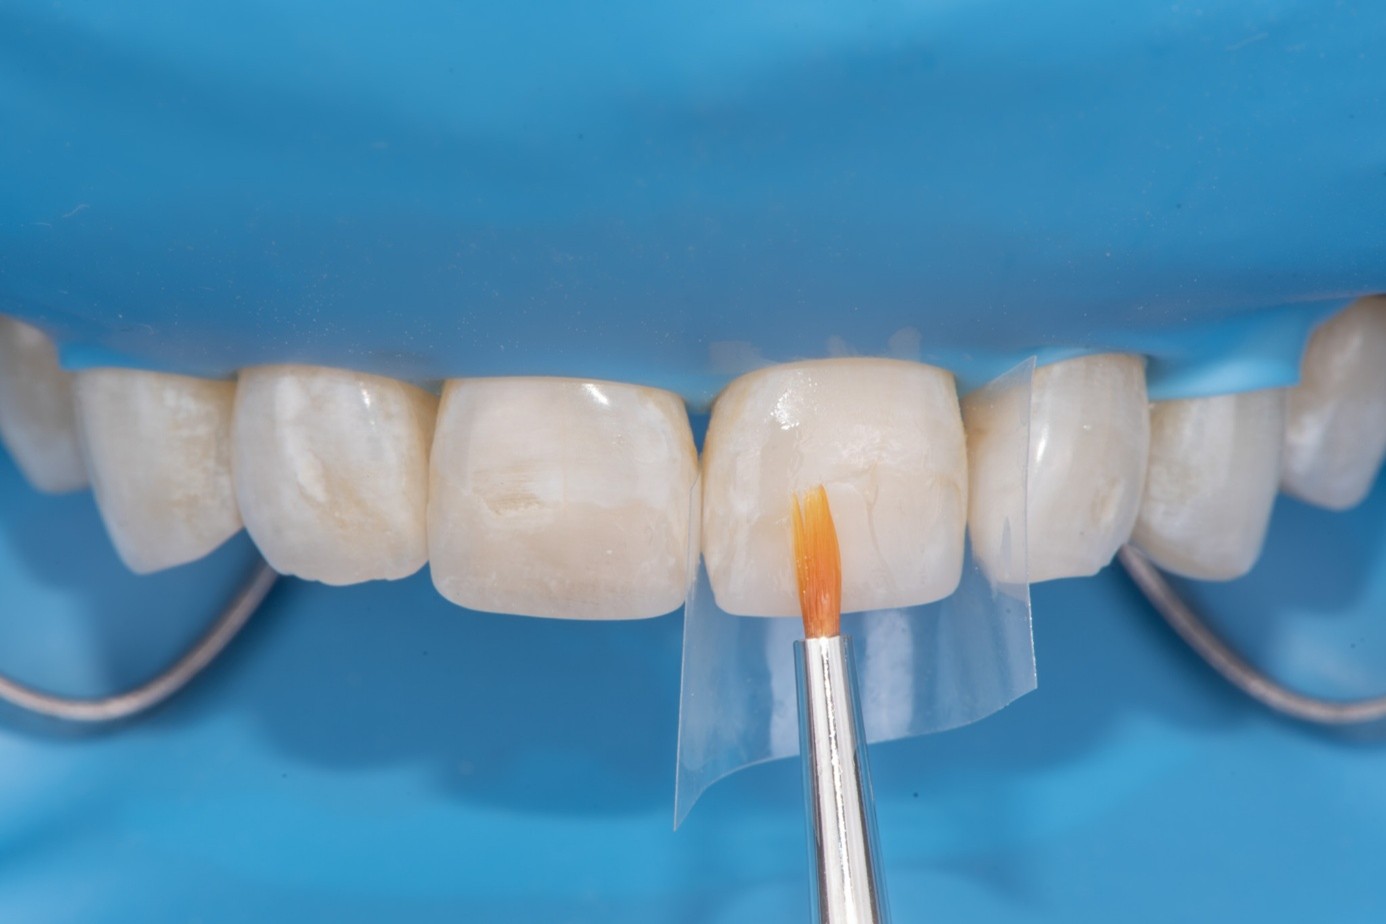

After achieving rubber dam isolation, the fractured composite segment was first air-abraded with aluminum oxide particles to clean and roughen the surface. It was then etched with phosphoric acid for 60 seconds, rinsed, dried, and treated with silane to enhance chemical adhesion (Figure 18 through Figure 20).8,9

The tooth surface was similarly air-abraded to remove biofilm and aged resin remnants, then selectively etched with phosphoric acid. Silane was applied intraorally to the exposed composite surface to promote bonding between the old and new composite layers.10 Following this, a universal bonding agent was applied to both the tooth surface and the fractured composite segment (Figure 21 through Figure 24).

(18.) The fractured composite fragment after sandblasting as a surface treatment, followed by etching and application of a single layer of silane, prepared for reattachment.

Figure 18

(19.) The fractured composite fragment after sandblasting as a surface treatment, followed by etching and application of a single layer of silane, prepared for reattachment.

Figure 19

( 20.) The fractured composite fragment after sandblasting as a surface treatment, followed by etching and application of a single layer of silane, prepared for reattachment.

Figure 20

(21.) Intraoral view after rubber dam isolation, showing prepared surfaces: both sandblasted and etched, with silanization applied only to the composite surface, ready for reattachment.

Figure 21

(22.) Intraoral view after rubber dam isolation, showing prepared surfaces: both sandblasted and etched, with silanization applied only to the composite surface, ready for reattachment.

Figure 22

(23.) Intraoral view after rubber dam isolation, showing prepared surfaces: both sandblasted and etched, with silanization applied only to the composite surface, ready for reattachment.

Figure 23

(24.) Intraoral view after rubber dam isolation, showing prepared surfaces: both sandblasted and etched, with silanization applied only to the composite surface, ready for reattachment.

Figure 24